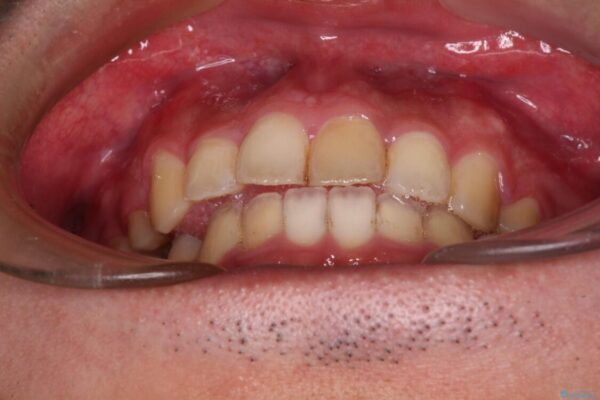

治療後

• 後戻りでデコボコの前歯 インビザライン矯正治療 治療後画像